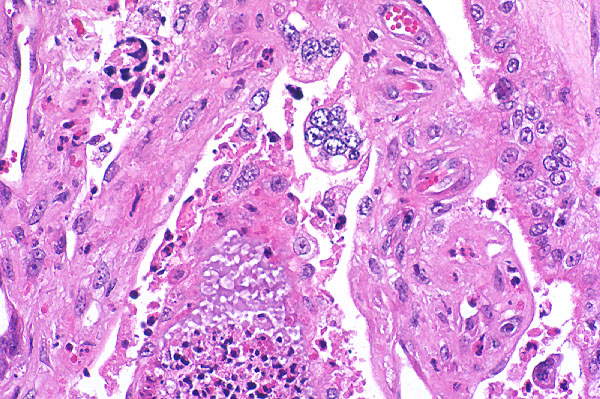

| 40x   |   Hematoxylin and Eosin | ||||

Villi are multifocally lined by large, multinucleated cells (syncytiotrophoblasts - arrow). Villar necrosis (*) is characterized by loss of normal architecture and replacement by eosinophilic cellular and karyorrhectic debris, and degenerate neutrophils.